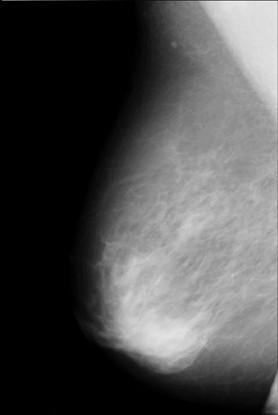

A vital information presented in the mammogram that can classify the breast lesions either malignant or benign. In this process the women age also consider to give decision along with clinical data of the patient. A particular advance to this problem is to extract called features from mammogram and then use a mathematical or statically model to classify lesions for the assessment of malignant versus benign. This approach is not exclusive to the classification using computers; a lot of radiologists are supporting for a related methodical approach during the analysis of mammograms [1]. As shown in Figure 1: A ranked malignant mass appears in mammogram which describes the severity of the disease.

Figure 1. Mammogram

Breast cancer causes a desmoplastic reaction in breast tissue. A mass is appeared as a bright hyper-dense object along with some deposits of calcium(calcifications) is also appears as intense areas in the mammogram.